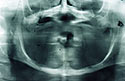

Patient's pre-operative appearance showing very thin non-keratinized mucosa with very little residual ridge.

The mental nerves were positioned at the ridge crest, and provide little room for implant application in the

posterior.

Panoramic radiograph showing the severe atrophy due to long term denture wear.